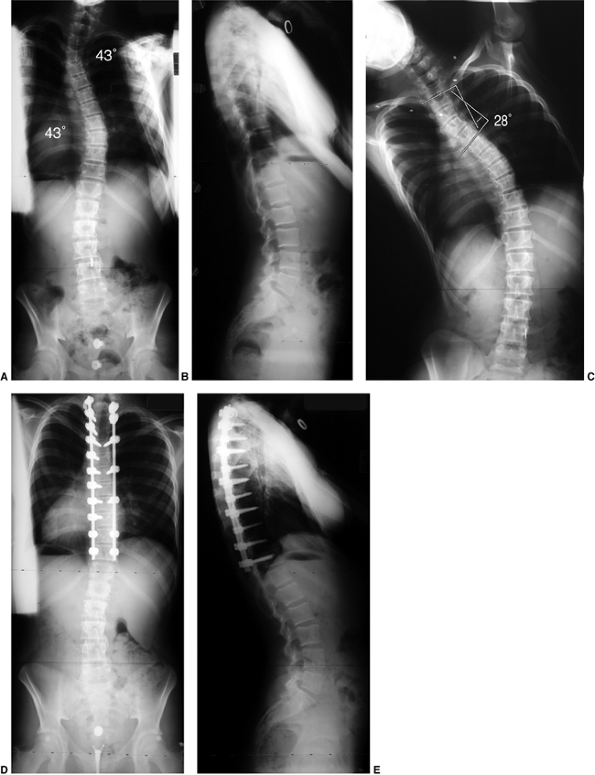

Figure 18.1 A:

This 16-year-old girl with severe scoliosis refused early treatment and had severe progression. Her clinical examination demonstrated marked trunk and rib deformity, and she had reduced pulmonary function. B: The posteroanterior radiograph demonstrates a right thoracic curvature of 125 degrees. With proper diagnosis and early treatment, deformity such as this should be completely avoidable in AIS.  |